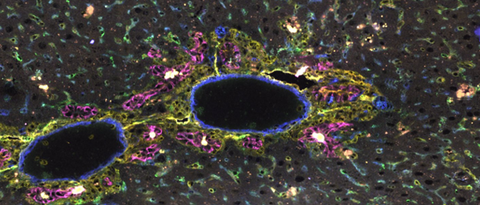

Seit mehreren Jahren erforschen Wissenschaftlerinnen und Wissenschaftler in Würzburg einzelne Zellen mit modernster Einzelzellanalyse. Der neue „In-situ-RNA-Imaging-Analyzer“ macht nun auch komplexe Krankheitsprozesse sichtbar.